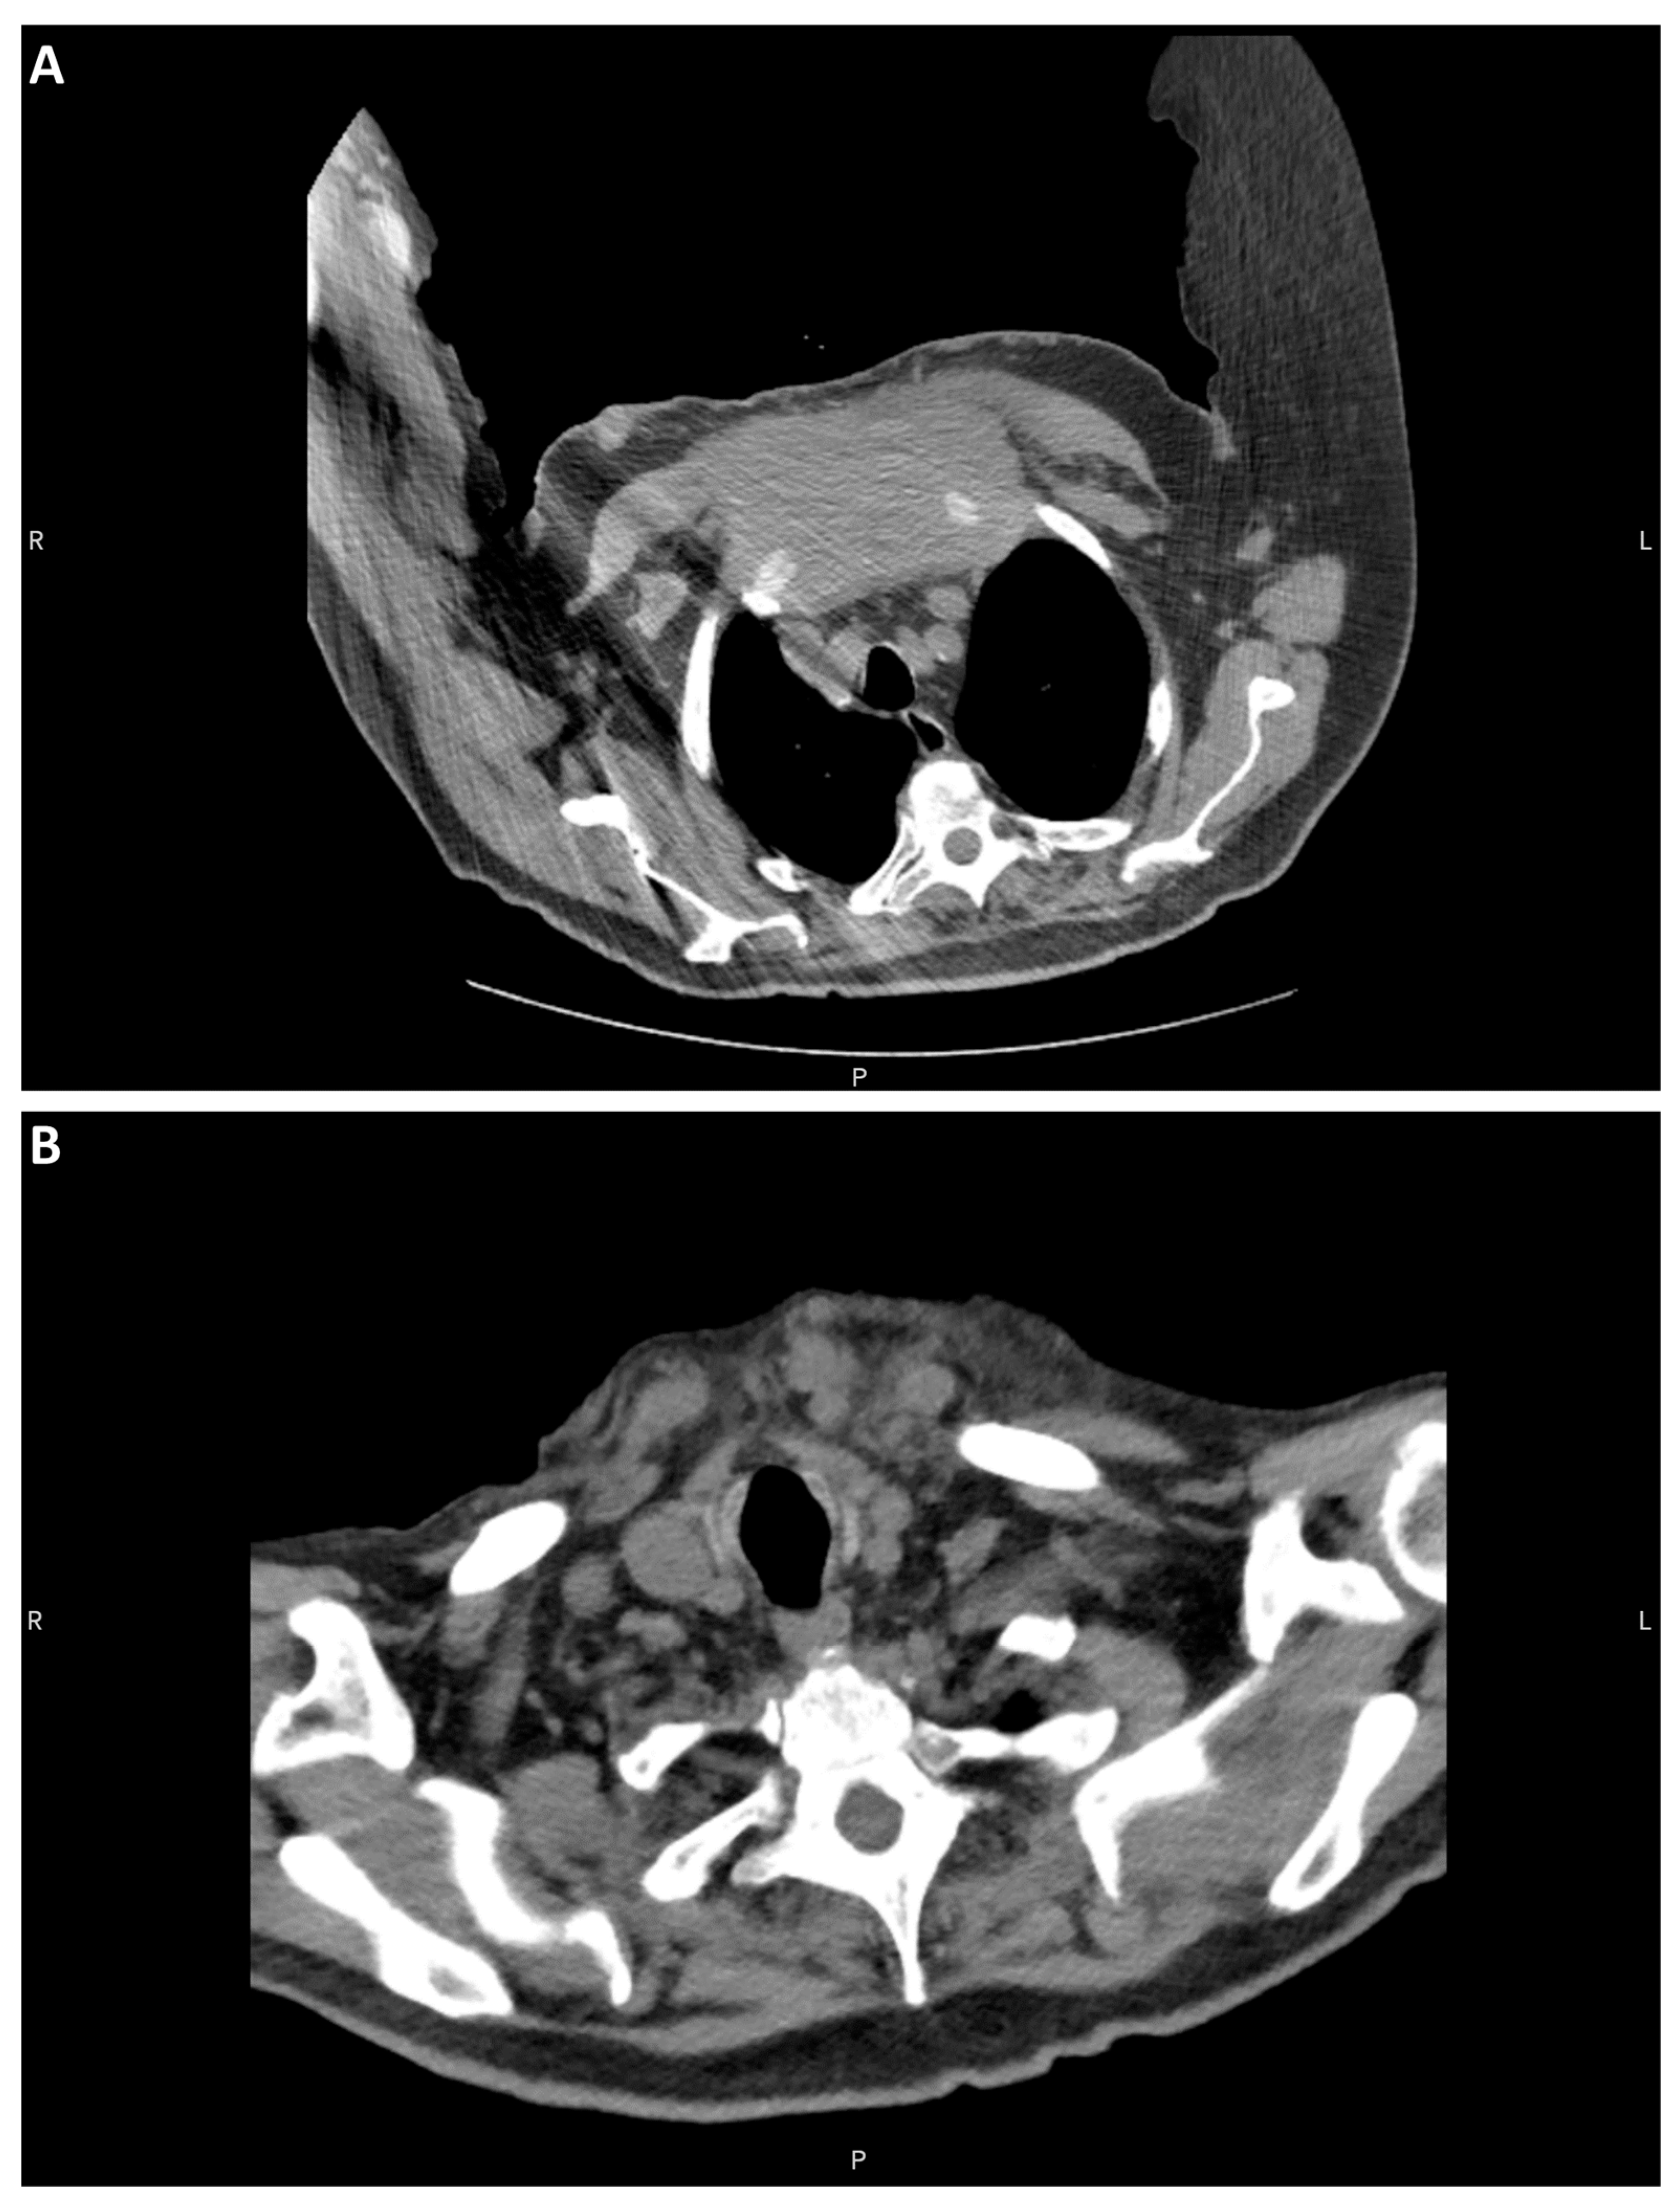

The patient examined was a 90-year-old with a medical history of hypothyroidism treated with levothyroxine and prostatic adenocarcinoma treated with radioactive seeds 20 years prior to the examination. The patient exhibited multiple raised skin lesions of up to 10 cm on his chest and weight loss amounting to 30 pounds. Computed tomography of the chest identified a large expansile soft tissue mass believed to arise from the sternal manubrium and the upper to mid-sternal body. The mass measured 12 cm in length, had a cross-sectional diameter of 11 cm, and infiltrated adjacent soft tissue structures and anterior mediastinal fat (Figure 1A). Given the possibility of the role of the thyroid in the differential diagnosis, a review of the roentgenogram was performed, which showed the absence of an atrophic gland (Figure 1B) without evidence of previous surgery.

Figure 1.

CT of the chest and neck. (A) Sternal mass. (B) Atrophic thyroid bed.